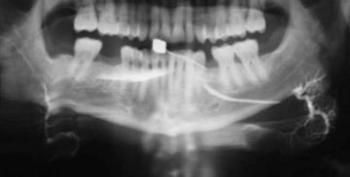

A szialográfia elvégzésének főbb indikációi a nyálmirigyek gyulladásos és nem daganatos betegségei, amikor általában a ductusrendszer elváltozásai dominálnak (12.1. ábra). Ebbe a heterogén csoportba tartoznak a gyulladások különböző formái (beleértve a Sjögrenszindrómát), a granulomatosus kórképek, obstrukcióval járó elváltozások, mint sialolithiasis és stricturák; sialosisok, fejlődési rendellenességek. Bár sok esetben a klinikai kép, hasonló, a radiológiai eltérések gyakran lehetővé teszik a klinikus számára a differenciáldiagnózis felállítását. A tumorok diagnózisában az eljárást ma már korlátozott értékűnek tekintjük. Az 1 cm-nél kisebb átmérőjű daganatokat nem tudjuk kimutatni, továbbá az extrinsic és intrinsic elhelyezkedésük sem ítélhető meg pontosan. Nyálkövek esetében a radiolucens kövek kimutatására hasznos lehet a szialográfia, bár a kő orificiumhoz közeli lokalizációja esetén nem javasolt, mivel a követ distalis irányba diszlokálhatja, amikor már az eltávolítása technikailag sokkal nehezebb. Kontraindikált akut gyulladás esetén, bármilyen eredetű is, valamint ritkán jódallergia is fennállhat.

12.1. ábra. Krónikus sialoadenitis sialographiás képe(Dr. Pataky Levente anyagából)